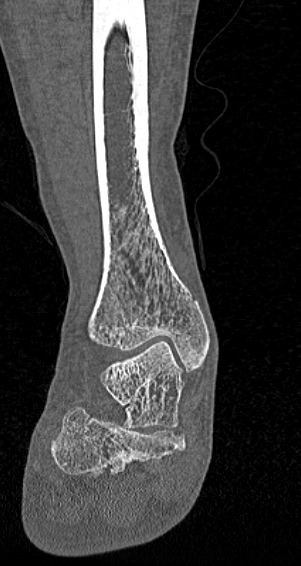

Костные ткани хорошо поглощают лучи рентгена, поэтому ярко визуализируются на снимках. В результате цифровой обработки полученных данных получаются точные трехмерные объемные модели исследуемой области. При этом изображение кости можно приблизить, повернуть в разные стороны, что значительно повышает точность диагностики заболеваний костного скелета.

В наших центрах проводится КТ различных отделов костного скелета. В протокол обследования 1 сегмента костного скелета входит прицельное исследование одной анатомической области. Например, КТ плечевой кости, КТ предплечья, КТ кисти, КТ стопы и других частей скелета.

Мультиспиральная КТ костей наиболее часто применяется в ортопедии, травматологии, хирургии, онкологии и ревматологии. Данное исследование позволяет диагностировать:

- Травматические повреждения костей скелета (различные переломы, ушибы надкостницы, вывихи, разрывы связок);